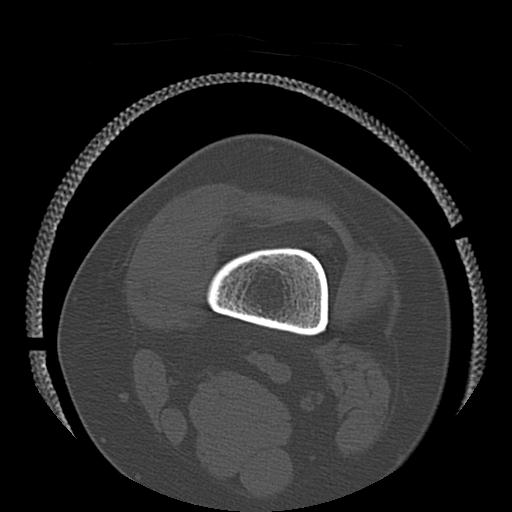

49554 3/13 膝 4R 3/16 4R 1/18 2R 78歳男性 膝蓋骨骨折